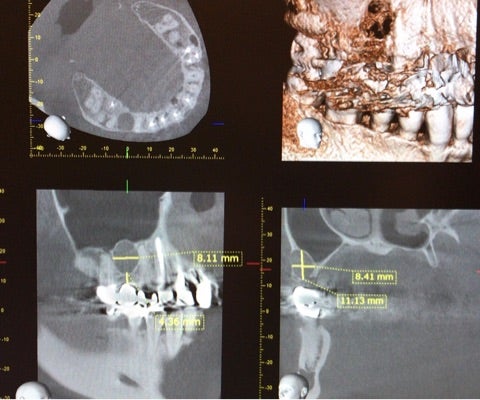

<CT画像②>

過去に根尖病巣を患い抜歯を行ってある部位に一致している事から術後性骨嚢胞の診断の下、嚢胞摘出術を行う事になりました。

今回も嚢胞は上顎洞に近接しているためピエゾサージェリーでの骨削を行い摘出を試みました。